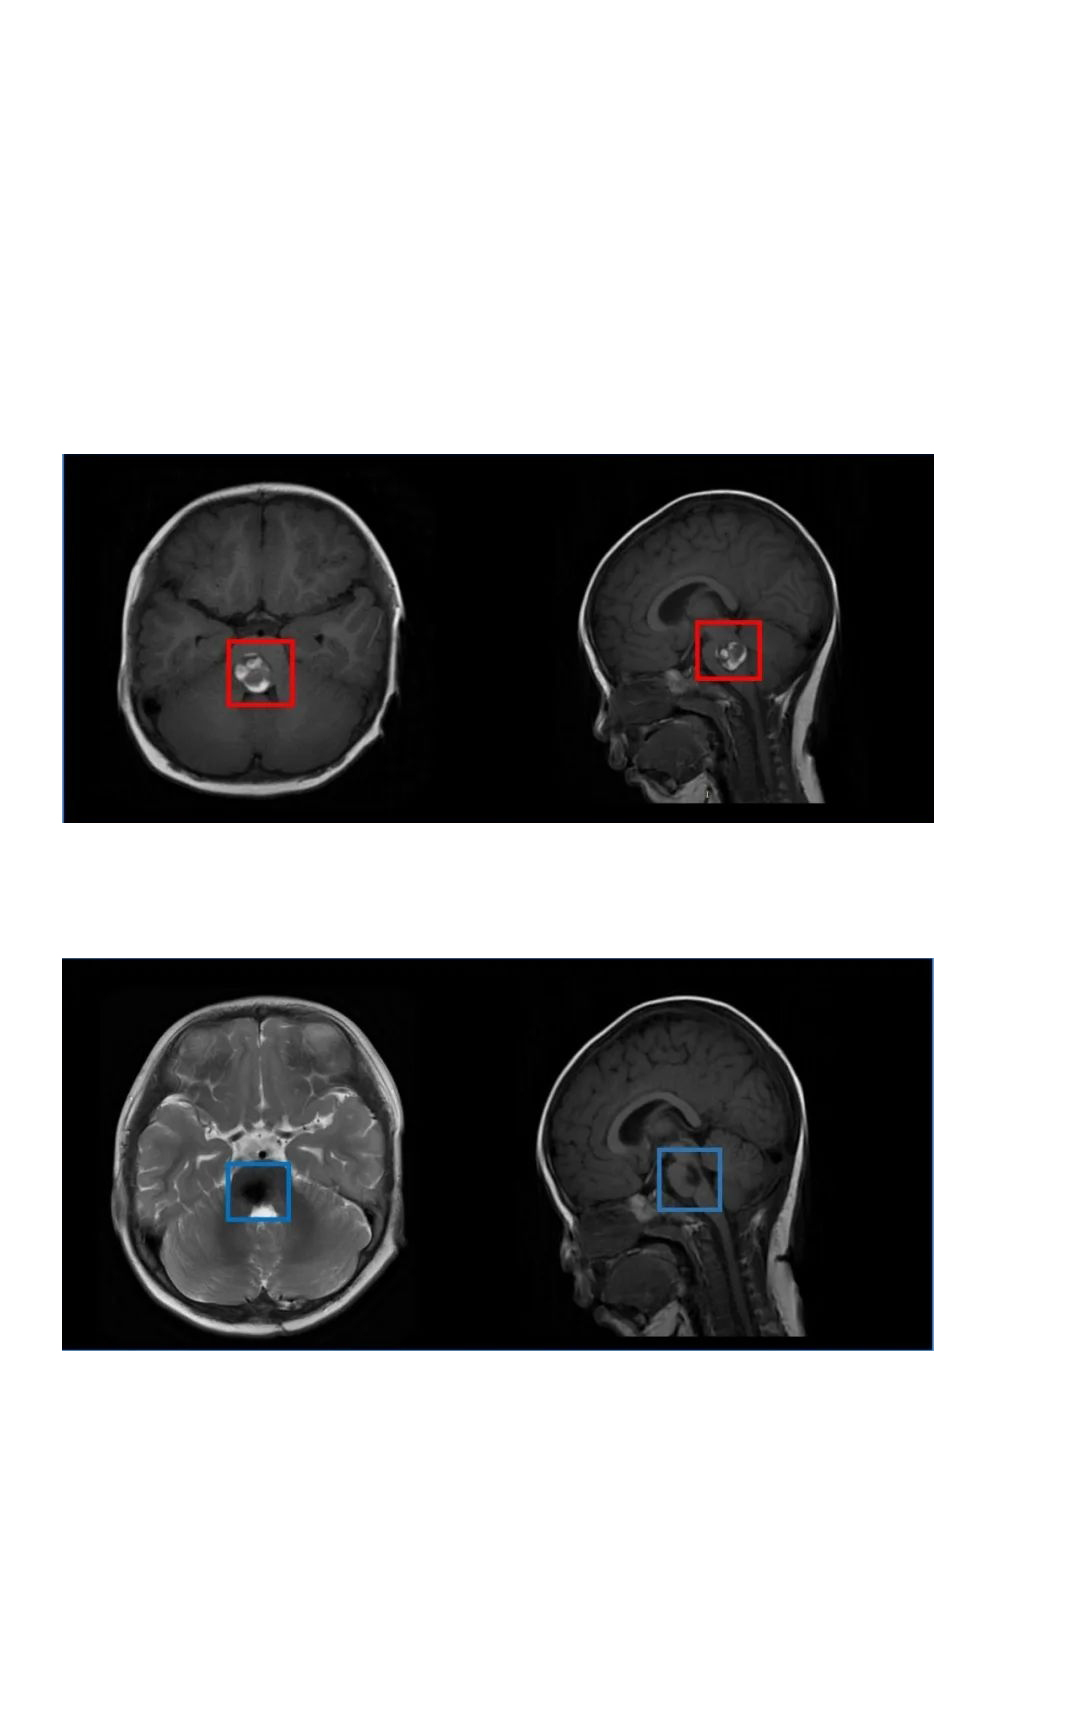

本来抱着应该就是小病小痛开点药就好了,直到医生听完症状描述后建议给伊伊做一个核磁检查,一家人的心突然揪了起来,较后核磁检查提示伊伊为脑干海绵状血管瘤,孩子持续20多天的双眼斜视、不自主扭头、走路不稳等症状是由于脑干海绵状血管瘤破裂出血所致。

(伊伊的脑干海绵状血管瘤病变位置)

与儿童医院协作的手术医生围绕病情展开了充分的讨论和评估,并根据患者病变的特点较终确定了相对创伤小的手术入路和手术方案。手术由巴特朗菲教授亲自操刀,儿童医院神经外科医生从旁配合,在电生理监测及高倍显微镜下,巴特朗菲教授游刃有余地避开了脑干中的一些重要神经核团、传导束,先将血肿清除,再慢慢地将2cm大小的脑干桥脑海绵状血管瘤完全剥离,整个手术历经了4个小时。

(伊伊术前术后对比)

术后二天,经历了如此高难度手术的伊伊就出了ICU,她术前频发的不自主扭头动作都消失,左侧眼睑稍下垂较前开始好转,双眼斜视较前好转,眼球活动度正常,其他术前症状均出现缓慢好转。巴教授也时常来伊伊病房看望这个可爱的孩子,“完全没有脑瘤教授的架子,特别亲切”,伊伊妈妈忍不住感慨。

而因为巴教授的手术技术,术后一周伊伊就出院了,术后一个半月复查,原有的斜视、走路不稳症状都消失了,面瘫减轻,行动能力完全正常,没出现任何新的并发症。